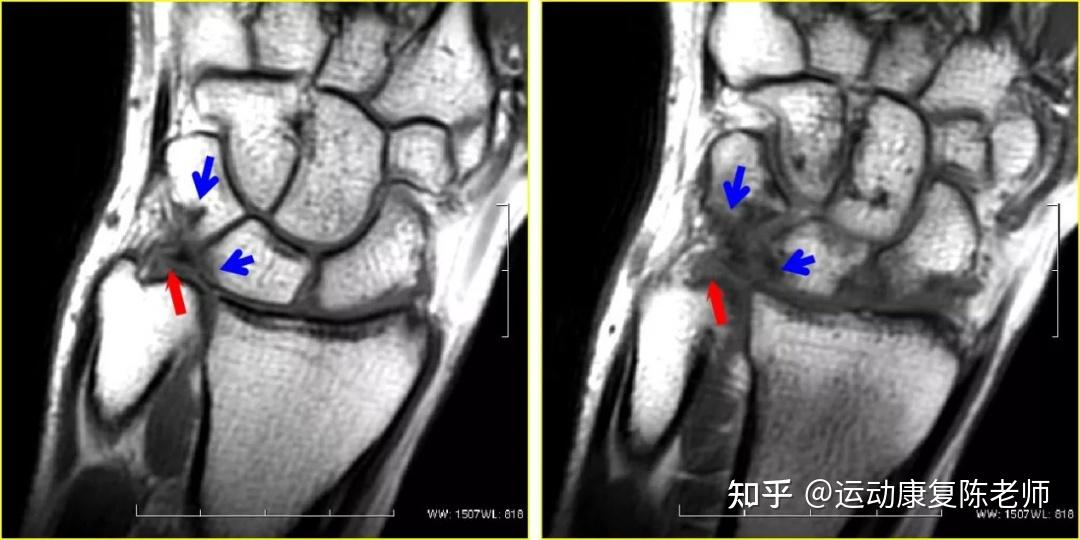

早读 | 三角纤维软骨复合体损伤的mr阅片技巧,深度好文!

镜下检查能够发现tfc中央型损伤或穿孔,月骨或三角骨的软骨损伤等表现